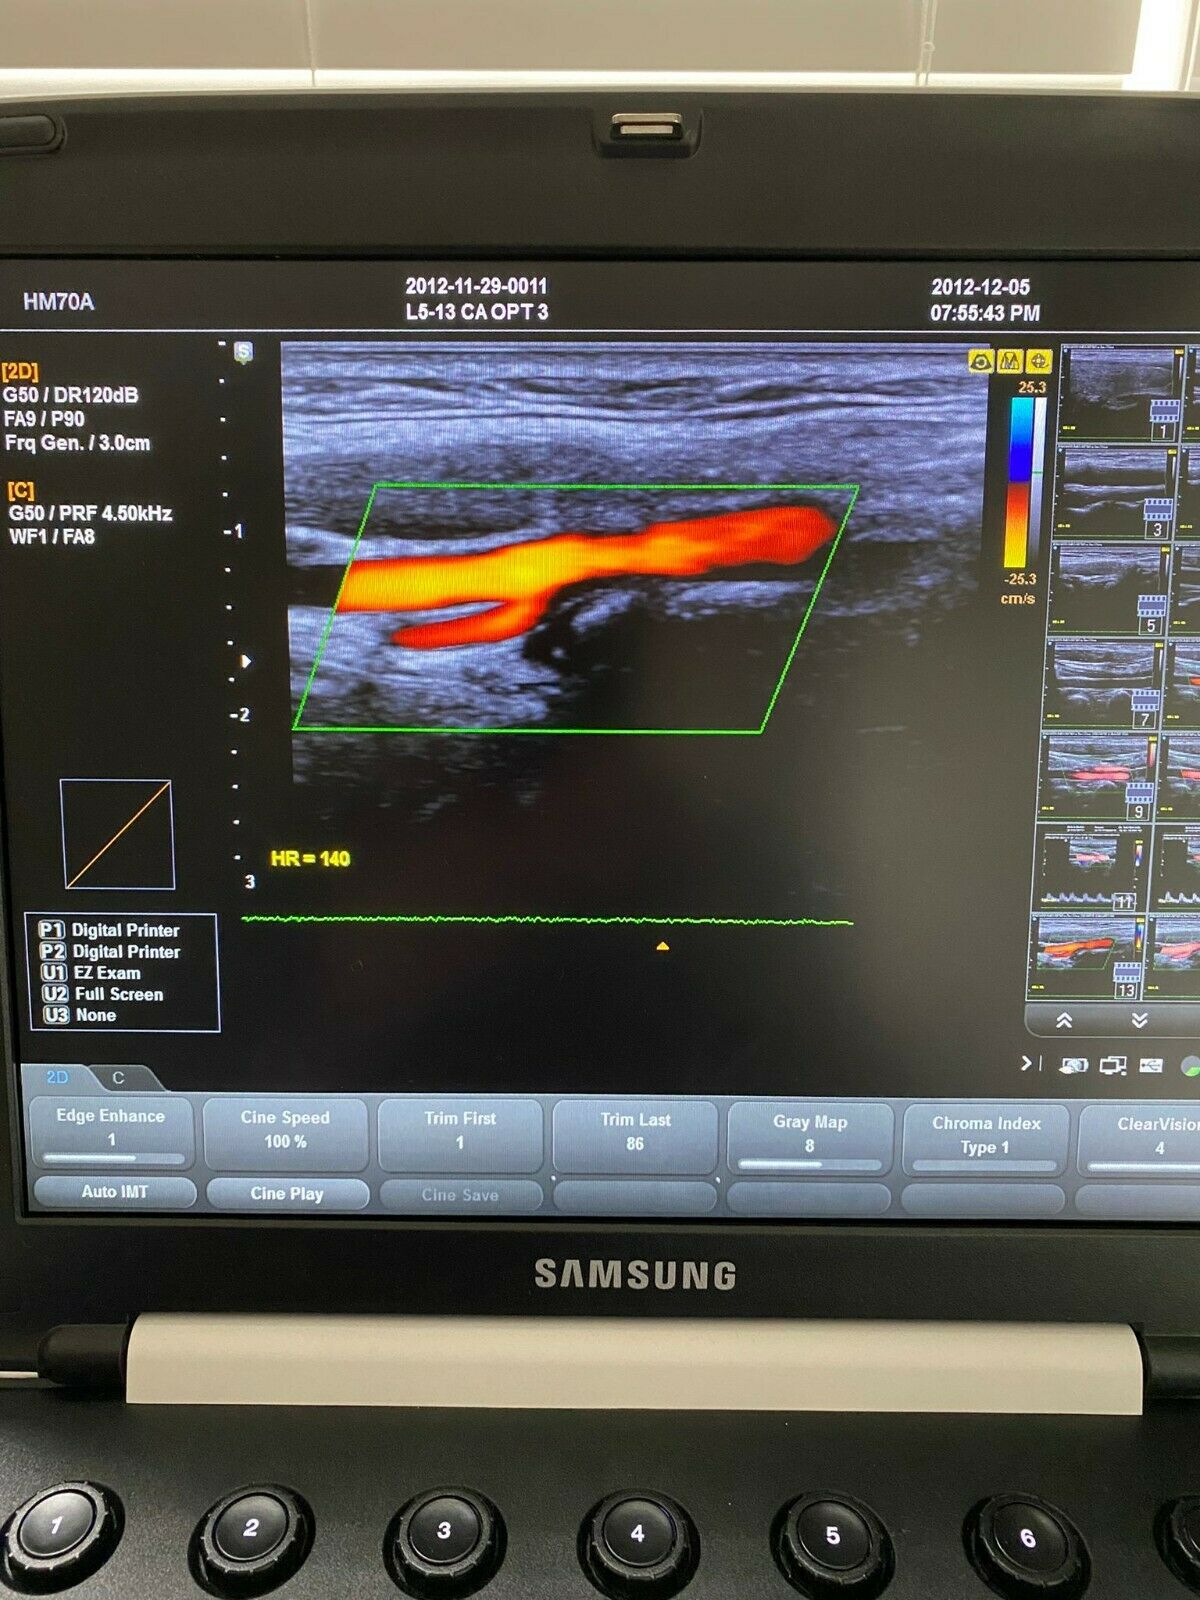

DIAGNOSTIC ULTRASOUND MACHINES FOR SALE

SAMSUNG HM70A PORTABLE ULTRASOUND WITH 2 PROBES

Sale price$ 11,150.88